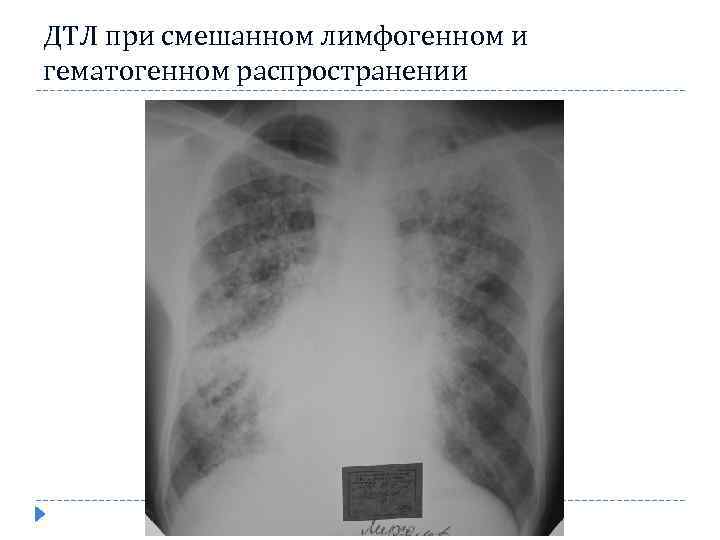

ДТЛ при смешанном лимфогенном и гематогенном распространении

ДТЛ при смешанном лимфогенном и гематогенном распространении